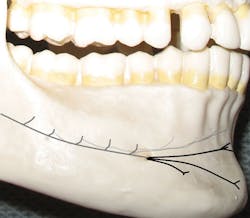

The inferior alveolar nerve, which travels through the mandibular canal, bifurcates just posterior to the mental foramen (see Figures 1, 2) to become the incisive nerve (continues to the midline through the mandibular canal) and the mental nerve (exits at the foramen and courses outside the bone toward the midline). When we provide a mandibular block, both nerves are anesthetized.

Figure 1: Abbreviated illustration of pathway: Incisive nerve (grays), mental nerve (black)